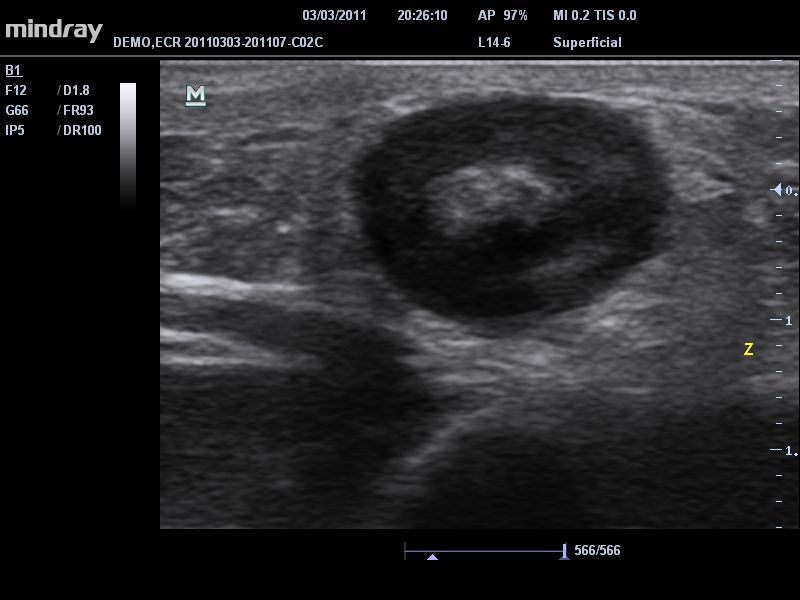

• B-Steer™ / iNeedle™: Функция маневрирования ультразвукового луча, улучшающая видимость иглы, нервных волокон и мелких сосудов.

• Высокочастотный линейный датчик 38 мм Mindray l14-6NE